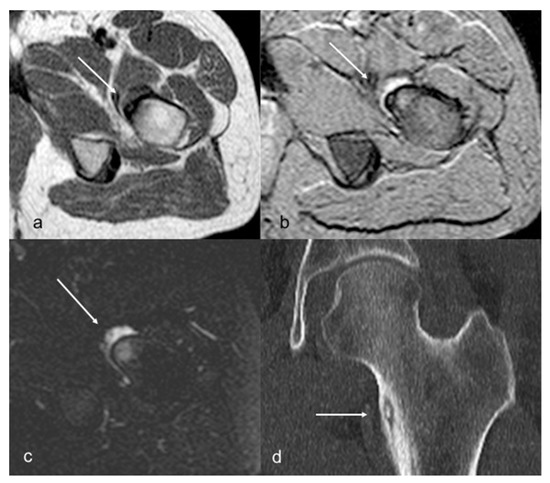

| 1 | F | 13 | right femoral neck, intra-articular, subperiosteal | pain, anterior thigh | no | no | N/A | - | yes | 2 | no | CT-guided RFA |

| 2 | F | 10 | right femoral neck, intra-articular, cortical | recurrent pain, right hip and knee | yes | no | yes | - | yes | 24 | recurrent hip synovitis | N/A |

| 3 | M | 18 | left femoral neck, juxta-articular subcortical | pain, left hip | yes | no | yes | - | yes | 5 | ileo-psoas enthesopathy | N/A |

| 4 | F | 15 | left acetabulum, intra-articular cortical | pain, left hip | no | yes | no | - | yes | 3 | no | N/A |